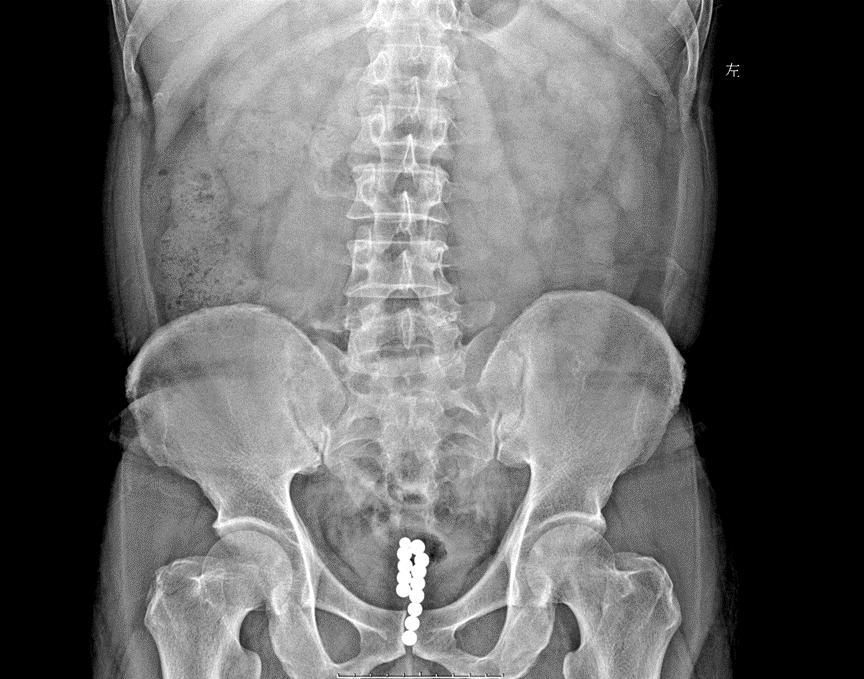

在医院进行的腹部平片(KUB)检查显示,由于钢珠带有磁性,已经连成一串,滞留在后尿道和膀胱。

泌尿外科医生经过半小时经尿道膀胱镜微创手术,才将珠子全部取出。13颗珠子大小不一,最大的直径有1cm。目前患者已出院回家休息。